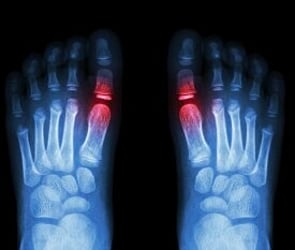

We provide the highest standard of podiatric care, utilising international gold standards of diagnosis and treatment.

Extracorporeal shock wave therapyESWT stimulates the body’s natural healing process